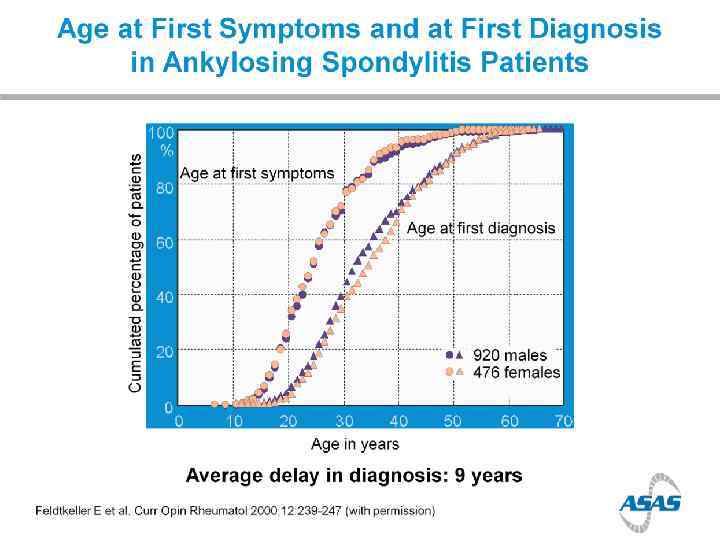

Prevalence of Axial Sp. A in US (NHANES study) chronic back pain in 20% of population IBP in 7% of population; > in younger adults Ax. Sp. A (including AS) in 1. 4% AS in 0. 5% AS nr. Ax. Sp. A MALES=FEMALES (Ax. Sp. A); M: F=2: 1 (AS) 12% in 2 years